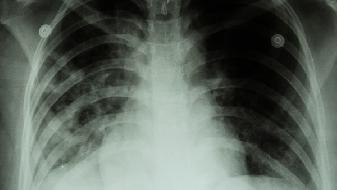

德特里克堡生物实验室,在2019年7月的时候,突然就关闭了,美国疾控中心呢,以国家安全作为理由,拒绝去公布关闭的细节。那个基地的附近,在2019年的时候,暴发过不明原因的肺炎,其症状跟新冠肺炎高度相似。国际社会多次提出要求,让世卫组织去调查德特里克堡,美国直到现在都装聋作哑。